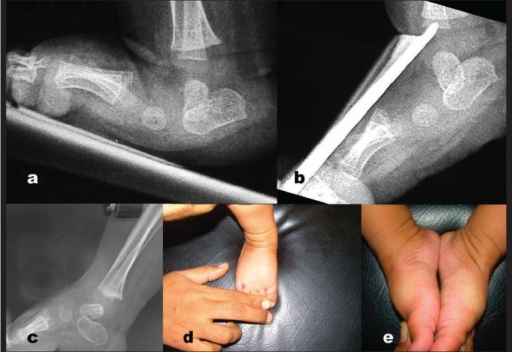

Lateral weight-bearing radiograph of an infant foot demonstrating congenital vertical talus. The talus is vertically oriented with the talonavicular joint irreducibly dislocated dorsally. The navicular articulates with the dorsal neck of the talus. The calcaneus is in equinus. This creates the characteristic 'rocker-bottom' or 'Persian slipper' deformity. A forced plantar flexion view would show persistent malalignment (distinguishing from oblique talus).

Source: Congenital vertical talus: treatment by reverse ponseti technique • Bhaskar A • PMC2739479 • CC-BY